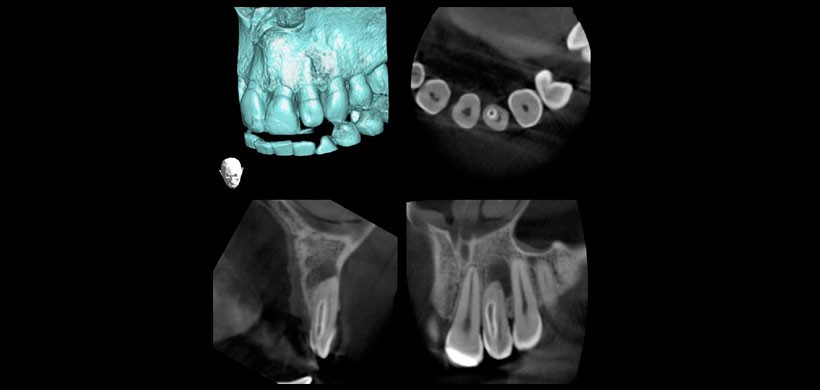

Fig 3. Tomografía computarizada de haz cónico. Vista Tangencial, transaxial y axial, se evidencia Fractura radicular visualizada en segundo premolar superior izquierdo.

Fig 4. Tomografía computarizada de haz cónico. Reformación 3 D, vista axial, sagital y coronal de una pieza dentaria con alteración en la anatomía y morfología (Dens in dent) de la pieza 2.2.